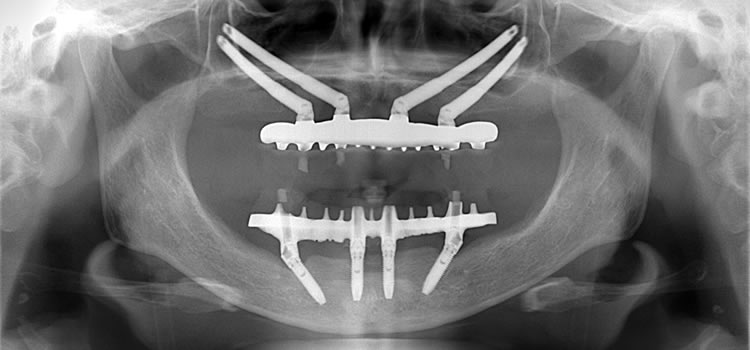

顎の骨が著しく失われているケースでは、通常のオールオン4の治療が難しい場合があります。そんなケースに対し、頬の骨にインプラントを埋入する高度な技術で対応することが可能です。患者様一人一人の状況に合わせ、最適な治療を行うことができるのはオールオン4クリニックの特徴です。